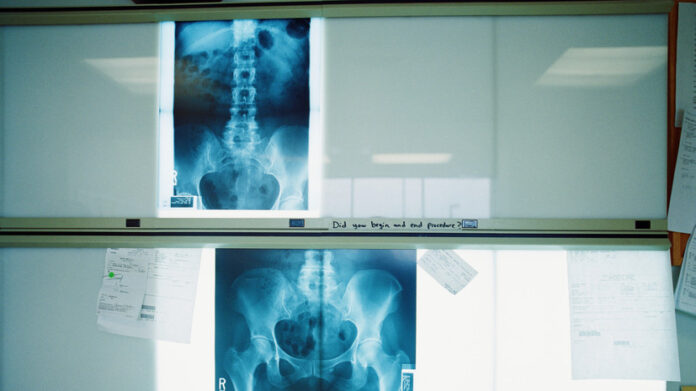

Новогодние хлопоты с подарками и продуктами требуют внимания к позвоночнику. Поднимая тяжести, приседайте с прямой спиной, распределяя нагрузку на ноги. Тем, у кого есть грыжи или протрузии, лучше отказаться от переноски объёмных грузов — попросите помощи у близких или используйте сумку-тележку.

Боль, сохраняющаяся больше недели после падения или физической нагрузки, — повод записаться на приём. Современные методы диагностики позволяют быстро определить причину дискомфорта и подобрать лечение. Доктор Наумов напоминает: даже незначительные травмы нуждаются в контроле, если ограничивают подвижность или сон.